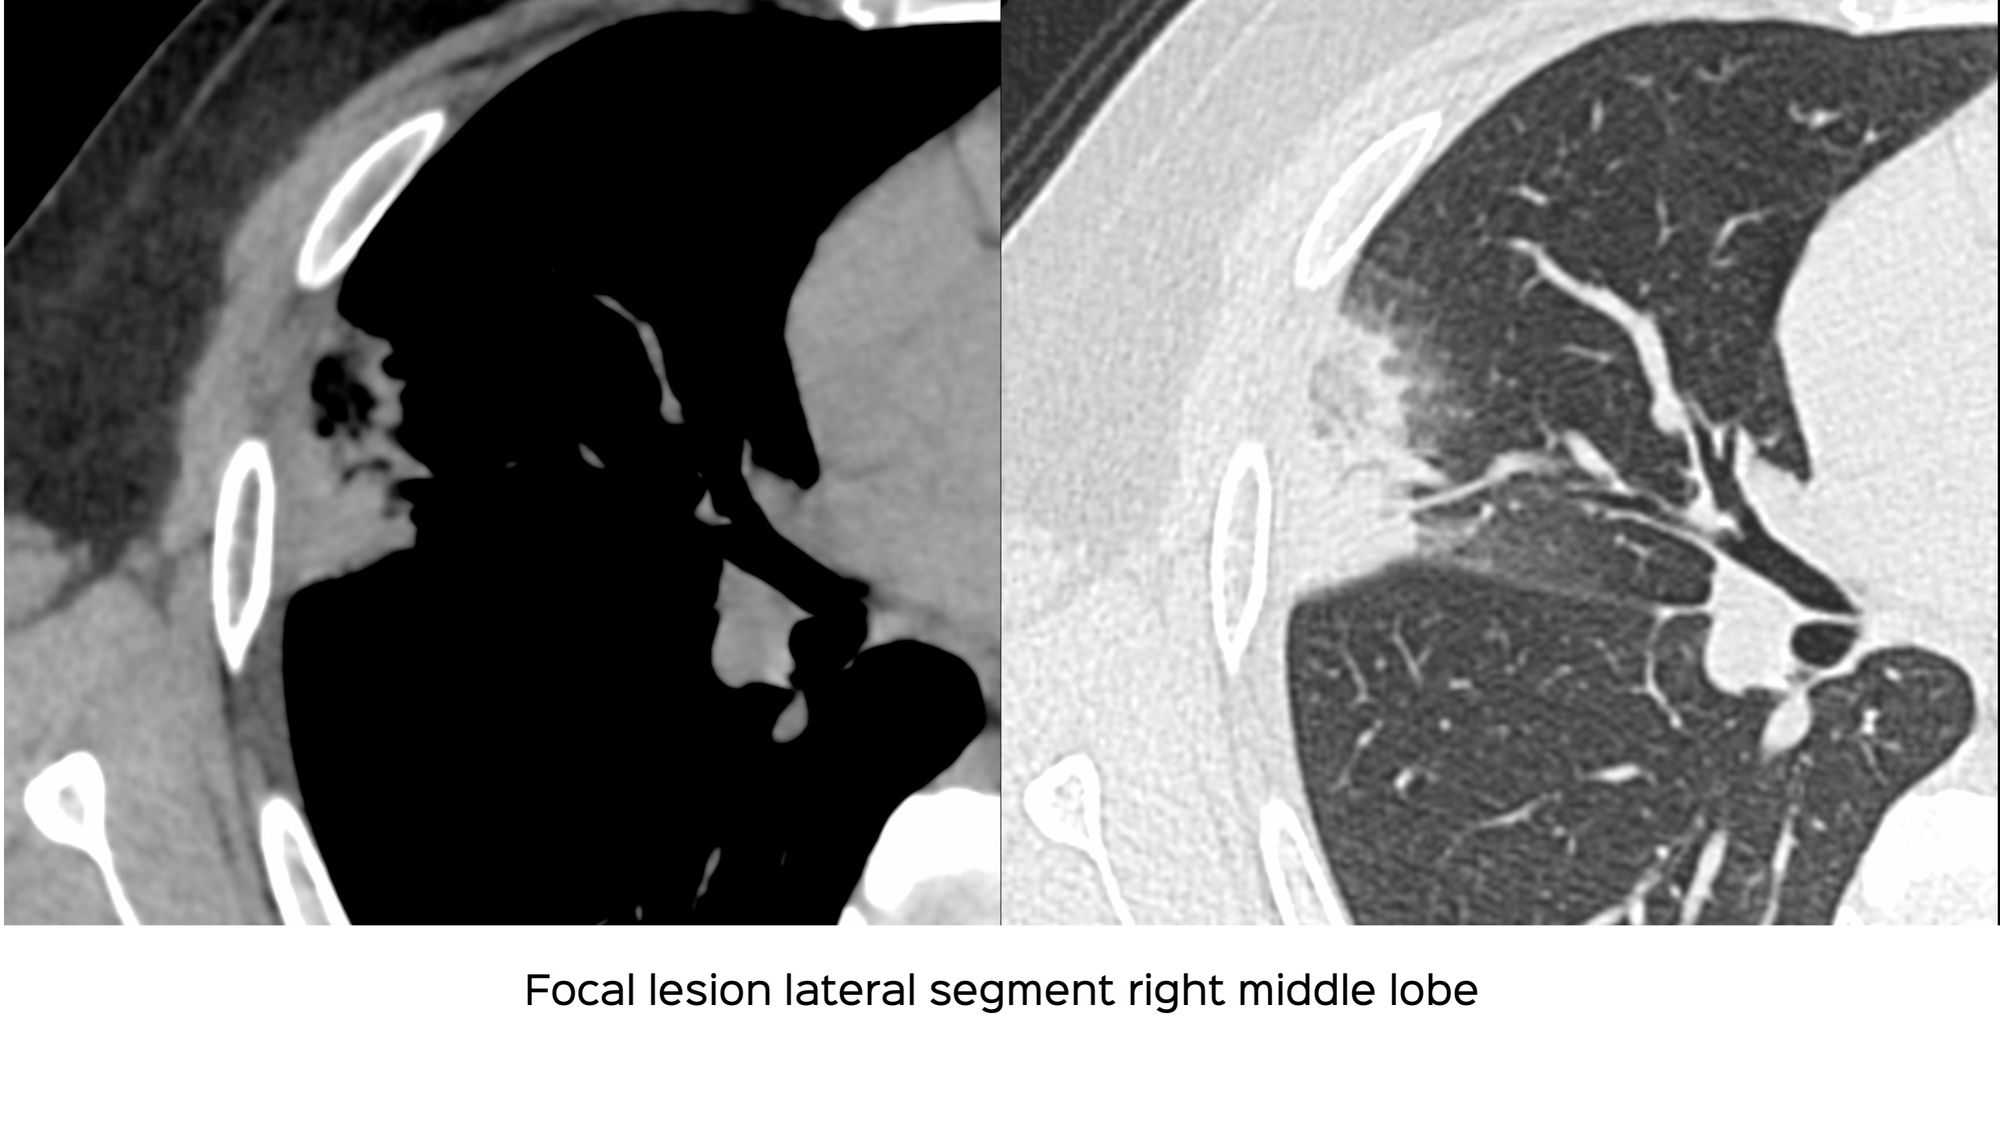

A 34-years old presented with one episode acute chest pain after a bout of extensive travel.

A CT scan was done.

- Pneumonic consolidation

- Lung infarct

- Invasive mucinous adenocarcinoma

- COVID-19

The video below discusses this case and similar other examples.